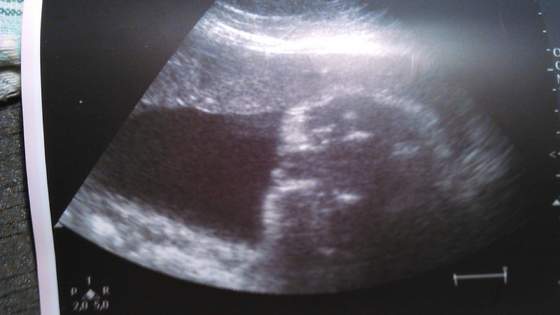

No ciocie :) mamy bułeczkę :) W końcu, w 33 tygodniu lekarz potwierdził płeć :D Nareszcie... hihi. To się naczekaliśmy.